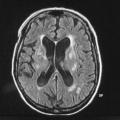

Syndrome parkinsonien d’origine vasculaire. Il est la conséquence de lésions vasculaires multiples affectant les noyaux gris centraux ou la substance blanche. L’IRM cérébrale permet de confirmer le diagnostic. Les caractéristiques cliniques sont : un syndrome parkinsonien plutôt symétrique, peu dopa-sensible ; prédominance des troubles aux membres inférieurs, marche avec freezing précoce ; syndrome pseudobulbaire.

L’imagerie cérébrale morphologique et fonctionnelle (fig. 2-7) occupe une place prépondérante dans la recherche d’arguments en faveur d’une pathologie neurométabolique (maladie de Wilson chez les sujets jeunes), de lésions vasculaires ou d’une hydrocéphalie à pression normale. L’IRM cérébrale permet également de mettre en évidence des anomalies évocatrices de certains syndromes parkinsoniens dégénératifs.